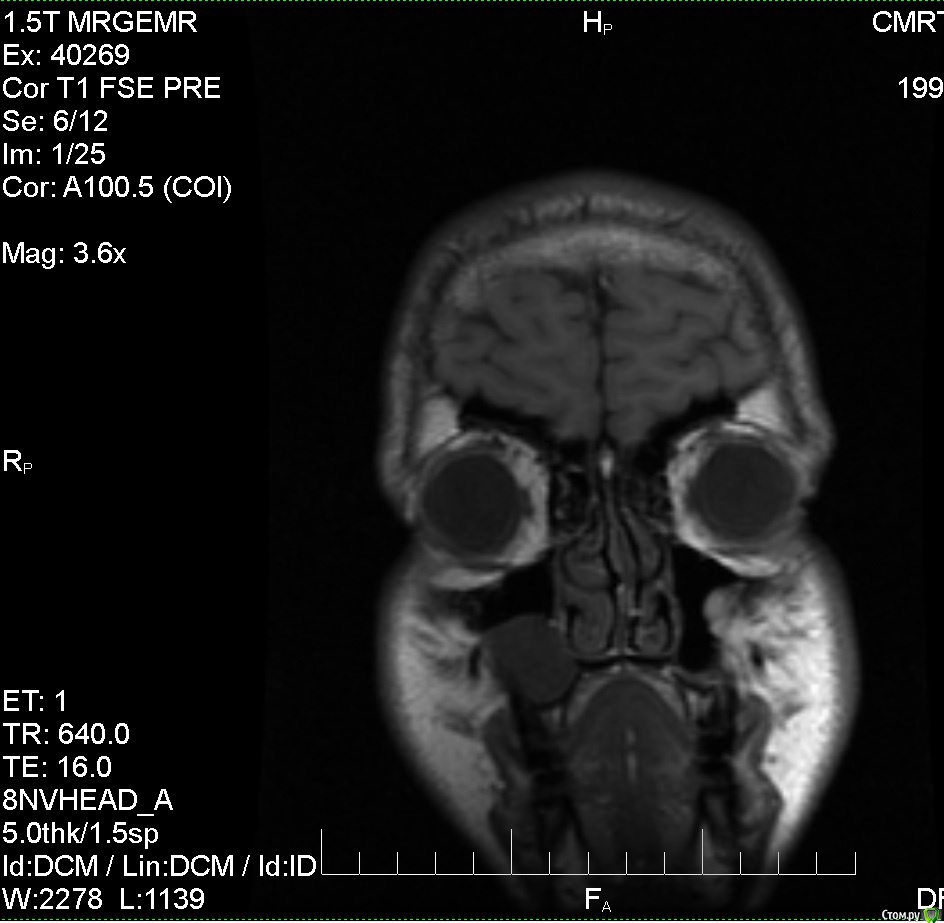

Сделал МРТ головного мозга с контрастом и без, в мозге патологий не выявлено, по заключению киста верхечюлестной правой пазухи. МРТ делал по причине непонятного тянущего ощущения в правой половине головы, не боль, просто стал себя чувствовать не как обычно. Ходил к лору, еле убедил вставить диск и посмотреть снимки, на, что получил ответ, что это от зубов и дорога моя к стоматологу. Высказала мнение, что достаточно вылечить зубы и корни, а кисту можно не трогать. Хочу получить мнение со стороны, и примерную тактику лечения в таких случаях.

Анамнез: уже 1.5 года немного воспалены/набухшие (гингивит?) края десны на верхней челюсти у 8,7,6,5 зуба, больше у 7 и 6. (Небольшая кровоточивость при чистки) На ощупь десны не болят, и зубы тоже. В них нет пломб. После заключения стал ощущать еле заметную тяжесть над перечисленными зубами.

Прилагаю фото снимков.